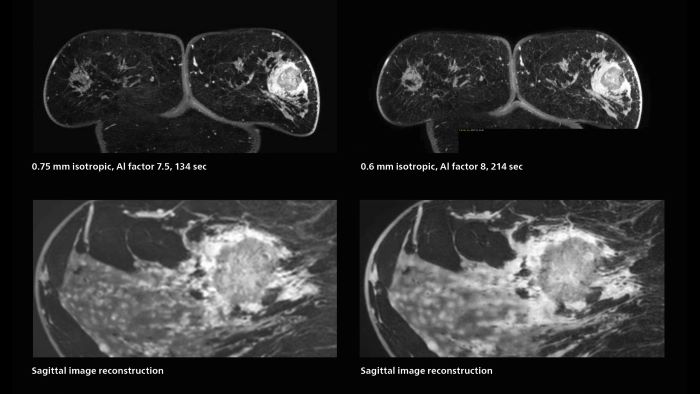

Fast, dynamic breast imaging for diagnostic confidence

Speed and high image quality are also important factors determining the diagnostic value of breast MRI. “When the spatial resolution is not high enough for making the diagnosis of breast cancer, a very difficult decision must be made,” says Dr. Katahira. “Since SmartSpeed now allows us to increase the resolution, we can often easily provide a confident answer. In the past with SENSE we used 1.2 mm isotropic voxels in breast imaging after contrast admission. With Compressed SENSE that is 0.8 mm. Now with SmartSpeed we can acquire 0.6 mm isotropic voxels and the images are so clear that even tiny details are clearly visible.”

3D MRI of breast cancer

Scanning was performed with two different voxel sizes. AI enabled volume MRI allows image reconstruction in other directions. Biopsy revealed invasive ductal carcinoma in this patient. Performed on Elition X.

Fast AI-enabled MRI of breast cancer: comparing 3D acquisitions with 0.75 mm and 0.6 mm isotropic voxels.

The hospital’s routine ExamCards for breast imaging include:

• ExamCard for 0.7 mm isotropic, 2:09 min, acceleration factor 7.5

• ExamCard for 0.6 mm isotropic, 3:37 min, acceleration factor 8